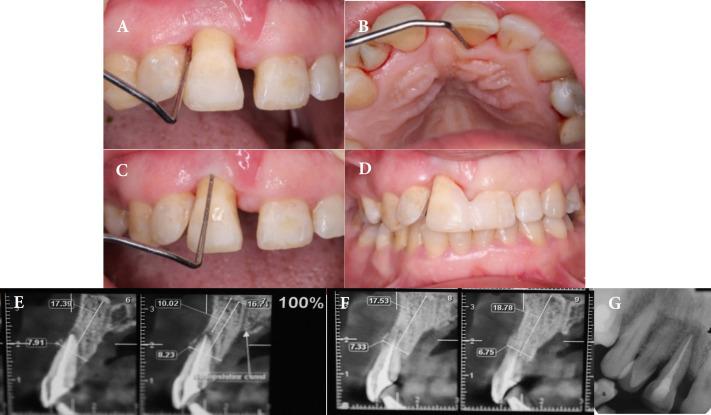

Endodontic-periodontal lesions have always been a challenge for treatment due to the reduced success rate in comparison to endodontic or periodontal lesions alone. This case report describes surgical/endodontic management of supra-erupted non-vital maxillary incisor with primary periodontal and secondary endodontic lesions with mobility grade III and severe horizontal and vertical loss of attachment apparatus in a 55 years old woman with aggressive periodontitis. The successful results at one-year follow-up revealed that with an appropriate case selection strategy, proper regeneration method and soft tissue enhancement, severe combined endo-perio lesions may treat.

牙髓-牙周联合病变的治疗一直是一项挑战,因为与单纯的牙髓或牙周病变相比,其成功率较低。本病例报告描述了一名55岁患有侵袭性牙周炎的女性,其右上颌无活力且伸长的切牙伴有原发性牙周病变和继发性牙髓病变,牙齿松动III度,附着装置严重水平和垂直丧失,对其进行了外科/牙髓治疗。一年随访的成功结果表明,通过适当的病例选择策略、合适的再生方法和软组织增强,严重的牙髓-牙周联合病变是可以治疗的。